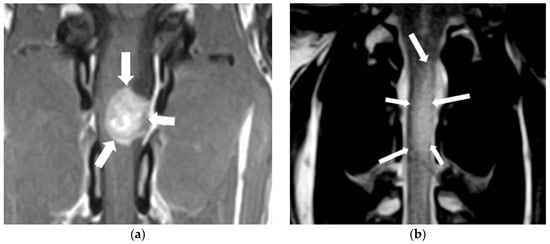

2.1. Intracranial Neoplasia

2.2. Cerebrovascular Disease